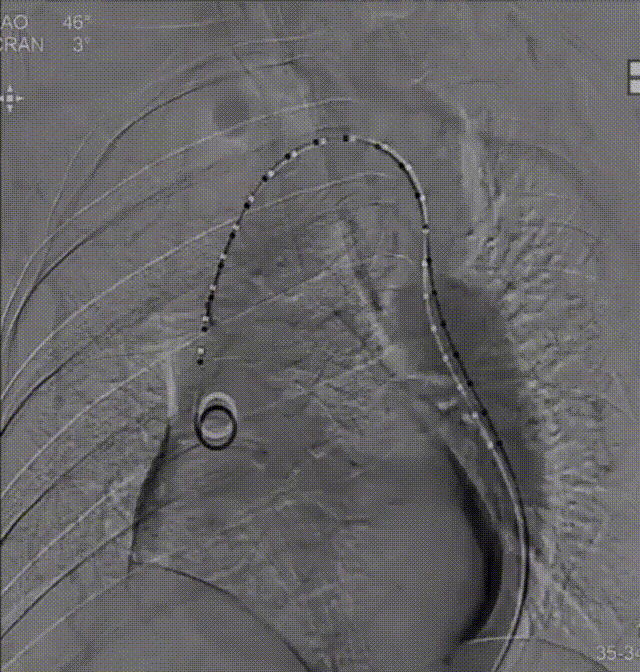

顺利完成CP支架组装后,经股动脉放置鞘管,成功将支架和球囊推送至血管缩窄段进行释放,血管造影结果提示预后效果理想。

术前、术后主动脉造影对比